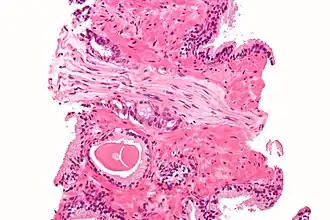

Each axon is surrounded by a layer of connective tissue called the endoneurium. The axons are bundled together into groups called fascicles, and each fascicle is wrapped in a layer of connective tissue called the perineurium. The entire nerve is wrapped in a layer of connective tissue called the epineurium. Nerve cells (often called neurons) are further classified as either sensory or motor.

Each nerve is covered on the outside by a dense sheath of connective tissue, the epineurium. Beneath this is a layer of fat cells, the perineurium, which forms a complete sleeve around a bundle of axons. Perineurial septa extend into the nerve and subdivide it into several bundles of fibres. Surrounding each such fibre is the endoneurium. This forms an unbroken tube from the surface of the spinal cord to the level where the axon synapses with its muscle fibres, or ends in sensory receptors. The endoneurium consists of an inner sleeve of material called the glycocalyx and an outer delicate meshwork of collagen fibres.[2] Nerves are bundled and often travel along with blood vessels, since the neurons of a nerve have fairly high energy requirements.